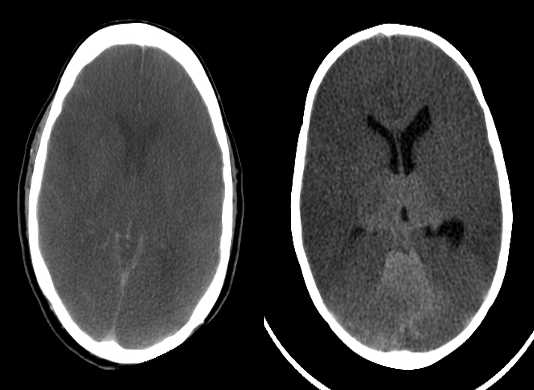

Absence of sulcal markings and poor differentiation of white and gray matter from diffuse bilateral cerebral hemispheric edema.

(a) Unenhanced CT imagedemonstrating vasogenic oedema

around a hyperdense brain metastasis . Note how the oedema extends through the white matter but spares the overlying grey matter cortex.

(b) Unenhanced CT demonstrating a wedge-shaped area of cytotoxic oedema

from an ischemic stroke involving the middle cerebral artery territory and both the grey matter cortex and the underlying white matter. Both are associated with mass effect causing distortion of the lateral ventricles.